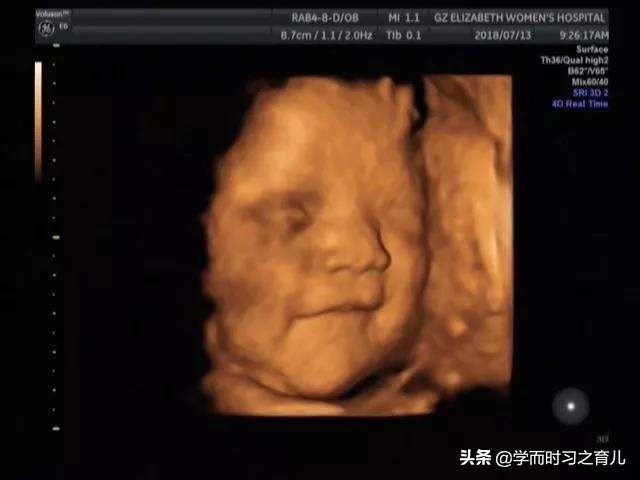

做四维彩超总是不顺利的其中一个原因就是宝宝胎动太厉害,要知道在做四维彩超时,医生需要对宝宝的各个器官进行检查,甚至还要测量胎儿局部的发育,比如双顶径、腹围、股骨长等等。

一旦宝宝胎动比较厉害,医生在检查的时候就会比较困难,这是因为当医生正要检查宝宝某个地方的发育情况时,宝宝忽然一动,医生就看不到了,或者说很模糊,看不清楚。